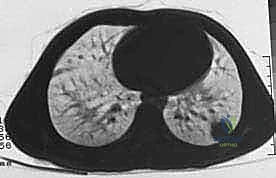

| الانتشار (النقائل) | لا تنتشر لأعضاء أخرى | تنتشر غالباً إلى الرئتين أو عظام أخرى |

* العلاج الكيميائي قبل الجراحة (Neoadjuvant Chemotherapy): يُعطى لتصغير حجم الورم، مما يسهل عملية الحفاظ على الطرف، ويقتل الخلايا السرطانية الدقيقة المنتشرة في الدم.

يتم تقييم مدى استجابة الورم للعلاج الكيميائي (Tumor Necrosis Rate) بعد الاستئصال، وهو مؤشر قوي لفرص الشفاء التام.